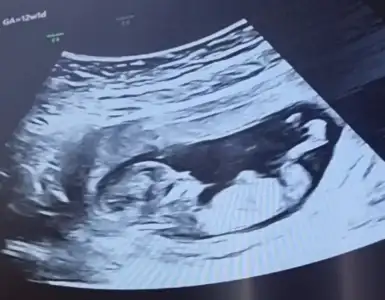

Çok net erkek .11 12 haftalık nub kız görünüyor du. Sonra yükseldi galiba. 12 +5 e kadar güven vermiyor nubYaa 11 hafta yanitti demekki çok paralel görünüyor du varmı 13 hafta bakmak isterim![]()

Kız görünüyorEki Görüntüle 2826055